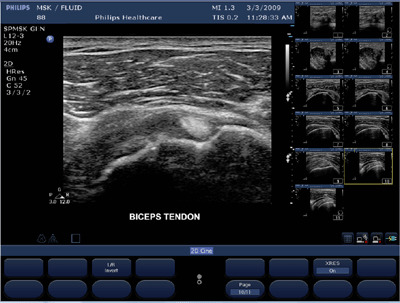

Well, move over, Big Three, as two mainstream radiology players enter the field. Philips and Toshiba are marketing high-end general-purpose hand-carried products that can perform routine radiology and cardiology scans in virtually any setting. Philips' CX50 and Toshiba's Viamo are laptop-sized ultrasound systems that were launched in Europe in March and will be displayed for the U.S. audience at the upcoming RSNA meeting.

Technological advancements are making portable ultrasound more widely accepted by clinicians. Initial compact units were fine for triage or image-guided procedures, but they didn't rise to the diagnostic level, said Jim Brown, marketing and product manager for Philips portable ultrasound systems.

Improved, diagnostic-quality images, longer battery life, and better tissue penetration are attracting increasing numbers of customers.

"We've improved over the years so overall image quality on hand-carried units is about the same as that of the console," said Al Lojweski, global general manager for GE's cardiovascular ultrasound division. "The advanced features-the 4D-may not be there, but basic 2D, B mode, color Doppler technology in compact systems is equivalent to a system you'd find in the ultrasound lab."